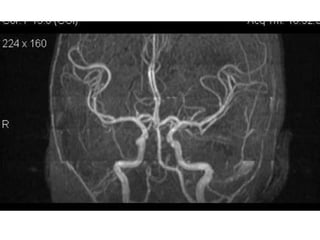

Arteries of the brain (cranial view) - MRA

1. Anterior cerebral artery

2. Anterior communicating artery

3. Basilar artery

4. branches (in insula) of middle

cerebral artery

5. Cavernous portion of internal carotid

artery

6. Cervical portion of internal carotid

7. Genu of middle cerebral artery

8. Intracranial (supraclinoid) internal

carotid artery

9. Middle cerebral artery

10. Ophthalmic artery

11. Petrous portion of internal carotid

12. Posterior cerebral artery

13. Posterior cerebral artery in ambient

cistern

14. posterior cerebral artery in

interpeduncular cistern

15. Posterior communicating artery

16. Posterior inf cerebellar artery.

17. Quadrigeminal portion of posterior

18. Superior cerebellar artery

19. Vertebral artery